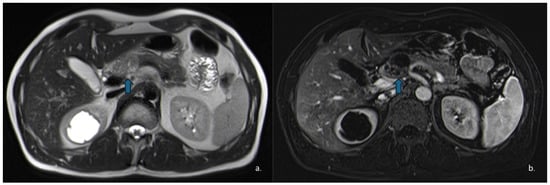

Figure 9.

MRI of a 37-year-old woman shows a lesion in the pancreatic head (arrow) with intermediate signal intensity on T2-w HASTE sequences (a) and mild enhancement of the solid component on dynamic arterial-phase sequence (b). Endoscopic ultrasound suggested the diagnosis of a solid pseudopapillary epithelial neoplasm (SPEN).

Pancreatic neuroendocrine tumours (PanNETs) are relatively rare neoplasms, with an annual prevalence of approximately 0.8 per million individuals. They typically present as solid lesions, although a cystic appearance may occasionally occur. Cystic PanNETs are believed to arise from degenerative processes, such as necrosis or ischemia within an initially solid PanNET [62] (Figure 10). When PanNETs exhibit a cystic morphology, they are usually non-functional, relatively small [63] and most commonly located in the body and tail of the pancreas [64]. Overall, cystic PanNETs demonstrate a lower malignant potential compared with their solid counterparts; in fact, a study by Khalil et al. reported no cases of metastasis or recurrence [65].

Figure 10.

The same patient as in Figure 7 underwent Contrast-Enhanced MRI, which showed a lesion (arrow) with inhomogeneous signal in the T2w—HASTE sequences (a) and areas of restricted diffusion in DWI and ADC maps corresponding to the mural nodules. (b,c) The patient subsequently underwent surgical resection, and histopathology confirmed a degenerated mucinous cystadenoma.